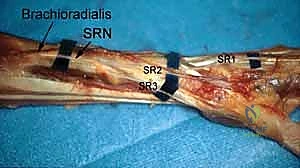

3. The 6R Portal (Radial to ECU)

- Location: On the radial side of the extensor carpi ulnaris (ECU) tendon.

- Anatomy: The ECU tendon lies within the sixth dorsal extensor compartment. Identifying the ECU is critical.

- Neurovascular Risks: Generally safe, but care must be taken to avoid the dorsal cutaneous branch of the ulnar nerve, which can course near this area.

- Function: Primarily used for instrumentation, especially when working on the ulnocarpal joint or TFCC. It allows for triangulation with the 4-5 portal.

5. The 1-2 Portal

- Location: This portal lies between the first and second dorsal extensor compartments.

- Anatomy:

- First Compartment: Contains the abductor pollicis longus (APL) and extensor pollicis brevis (EPB) tendons.

- Second Compartment: Contains the extensor carpi radialis longus (ECRL) and extensor carpi radialis brevis (ECRB) tendons.

- Neurovascular Risks: The superficial radial nerve (SRN) is highly vulnerable in this region. Its branches can be quite variable. Meticulous blunt dissection and careful palpation of the tendons are crucial.

- Function: Used less frequently than 3-4 or 4-5, but provides an excellent view for radial styloidectomy, visualizing the radioscaphoid joint, and addressing specific pathologies on the radial side.

Most of the complications related to use of the dorsal portals are related to injury to the sensory branches of the superficial radial nerve and the dorsal cutaneous branch of the ulnar nerve.